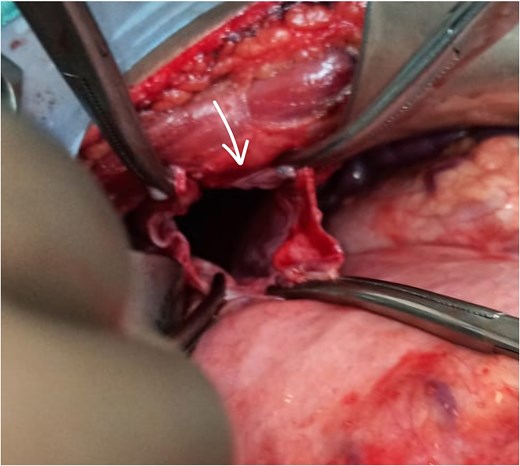

The patient underwent exploratory laparotomy. Left subcostal incision taken, intra-operatively adhesions were noted over the left hemidiaphragm near the defect, and herniation of the splenic flexure of colon along with part of stomach and greater omentum. The part of omentum was found gangrenous (Figs 3 and 4) and rest of the herniating contents was healthy and viable. The herniating content was repositioned in abdomen after adhesiolysis with omentectomy and primary repair of the left diaphragmatic defect using Prolene 1-0 RB (Fig. 5) after refreshening edges of the defect which were later sent for biopsy. The procedure was uneventful. One chest tube was placed in the left hemithorax and one abdominal draining tube was inserted in the subdiaphragmatic space.